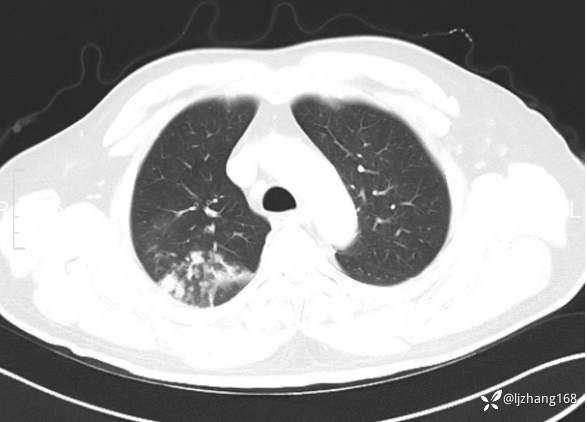

中年男患,右肺团片影,炎症0R肿瘤?

患者年龄:47岁

主诉:咳嗽、 咳痰伴气短20+天

简要病史: 20+天前患者因受凉后出现阵发性咳嗽,咳少量白色粘痰,痰易咳出,伴活动后气短,伴纳差、乏力、全身酸痛,伴多汗,无痰中带血及咯血,无发热、畏寒及寒战,无潮热、盗汗,无夜间阵发性呼吸困难及端坐呼吸,无声嘶,无头晕、头痛,无黑矇、晕厥及意识障碍,无腹痛、呕血及黑便等不适,遂就诊于当地医院予以输液等治疗后未见明显好转(具体诊疗不详),现为进一步诊治就诊于我院门诊,以“右肺占位”收入我科。病来饮食欠佳,近期体重下降(具体不详)。既往糖尿病病史7+年,未规律监测血糖,血糖控制不佳。否认“高血压、冠心病及慢性肾脏病”等慢性疾病史。否认“肝炎、结核、伤寒”等传染病史。否认食物、药物过敏史。否认外伤、输血史,预防接种史不详。

辅助检查:糖化血红蛋白12.3%。肺炎支原体IgG、IgM、呼吸道合胞病毒均未见明显异常。胸部CT:右肺上叶阻塞性肺炎。